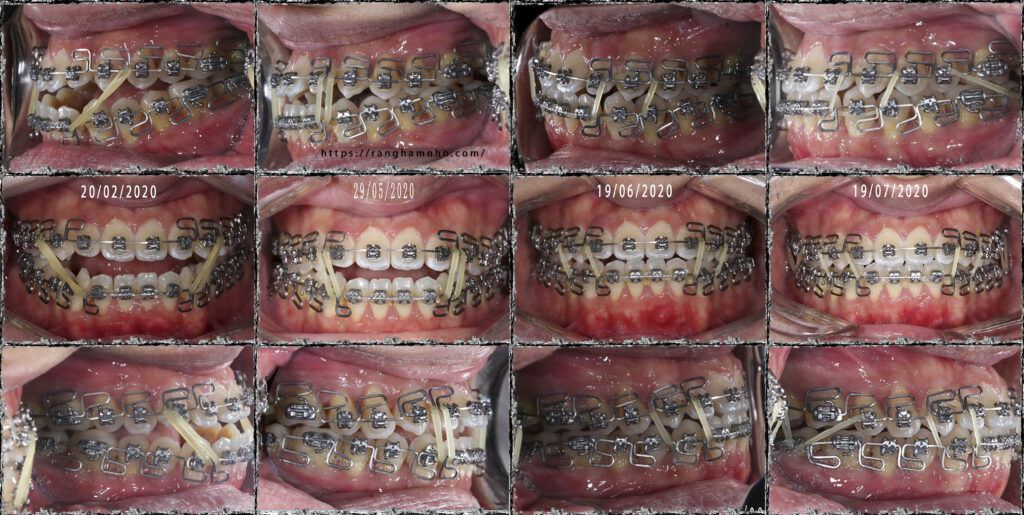

Bệnh nhân nam sinh năm 1993. Bệnh nhân đến với tình trạng khớp cắn ngược, hàm dưới phủ ngoài hàm trên, mặt lưỡi cày và các răng hàm dưới chen chúc nhiều. Răng hàm khớp cắn đối múi nhiều, không có sự lồng khớp tốt giữa hai hàm

Kĩ dây cung thẳng đa loop (kĩ thuật MEAW) được sử dụng để giải quyết tình trạng khớp cắn ngược. MEAW là một kĩ thuật điều trị bù trừ điều trị rất hiệu quả cho các trường hợp khớp cắn hạng III này, bệnh nhân không phải nhổ răng mà vẫn đạt được kết quả rất tốt.

Thời gian điều trị: 1.5 năm